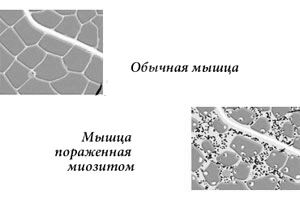

Такий стан може протікати безсимптомно, тільки зі змінами лабораторних даних. Але так буває не завжди. У деяких випадках урати можуть відкладатися в м'язах і суглобах, пошкоджувати тканини нирок і нервову систему. У цьому випадку виникають ниючі болі в ногах і попереку, неінтенсивні, але постійні болі в суглобах, порушення їх рухливості, невмотивоване зниження настрою, може з'явитися домішка крові в сечі.

Лабораторні симптоми, що дозволяють запідозрити сечокислий діатез у дорослих, - це висока або неодноразове підвищення кількості солей сечової кислоти в сечі, підвищення їх вмісту в крові. В біохімічному аналізі крові можуть бути присутніми маркери запалення і ферменти, які вказують на ушкодження м'язів. Також можуть бути ознаки інших захворювань, які провокують розвиток уратурія.